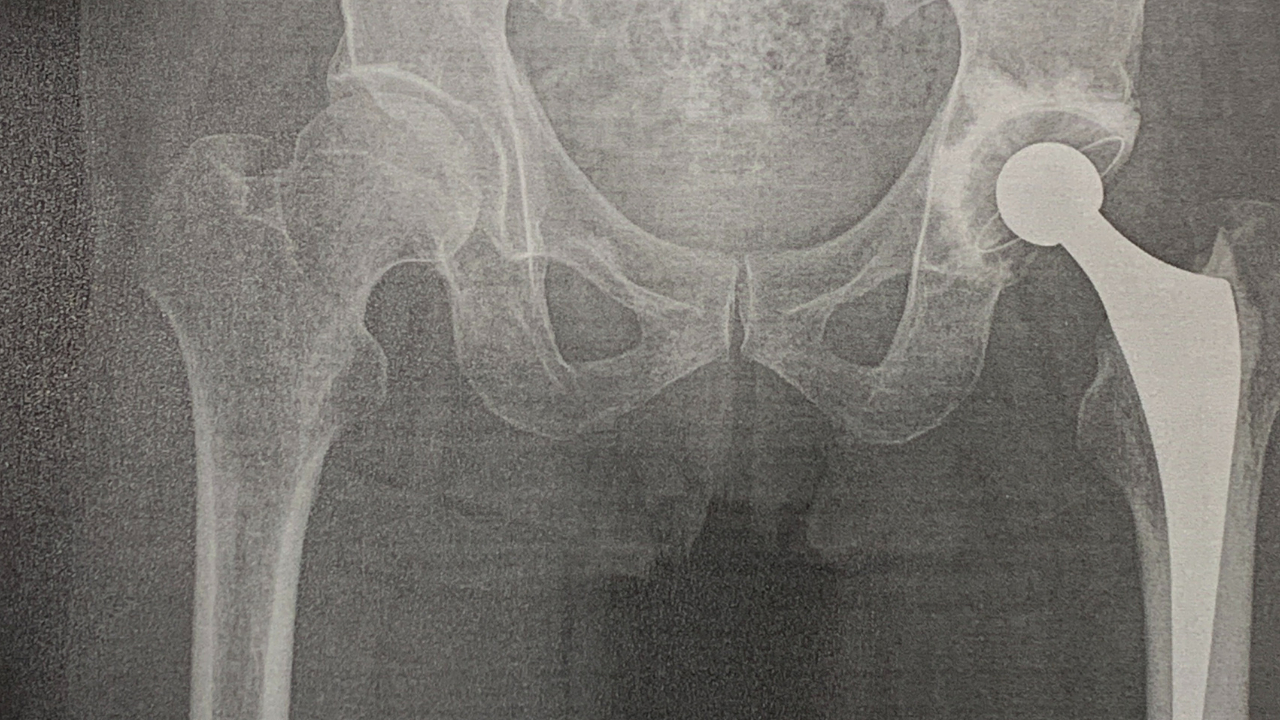

レントゲン撮影が有って

股関節の様子を診てくれて

経過を教えて貰っていました。

尤も、

レントゲン画像については

インスタへは流していませんが・・。

股関節 レントゲン画像.png